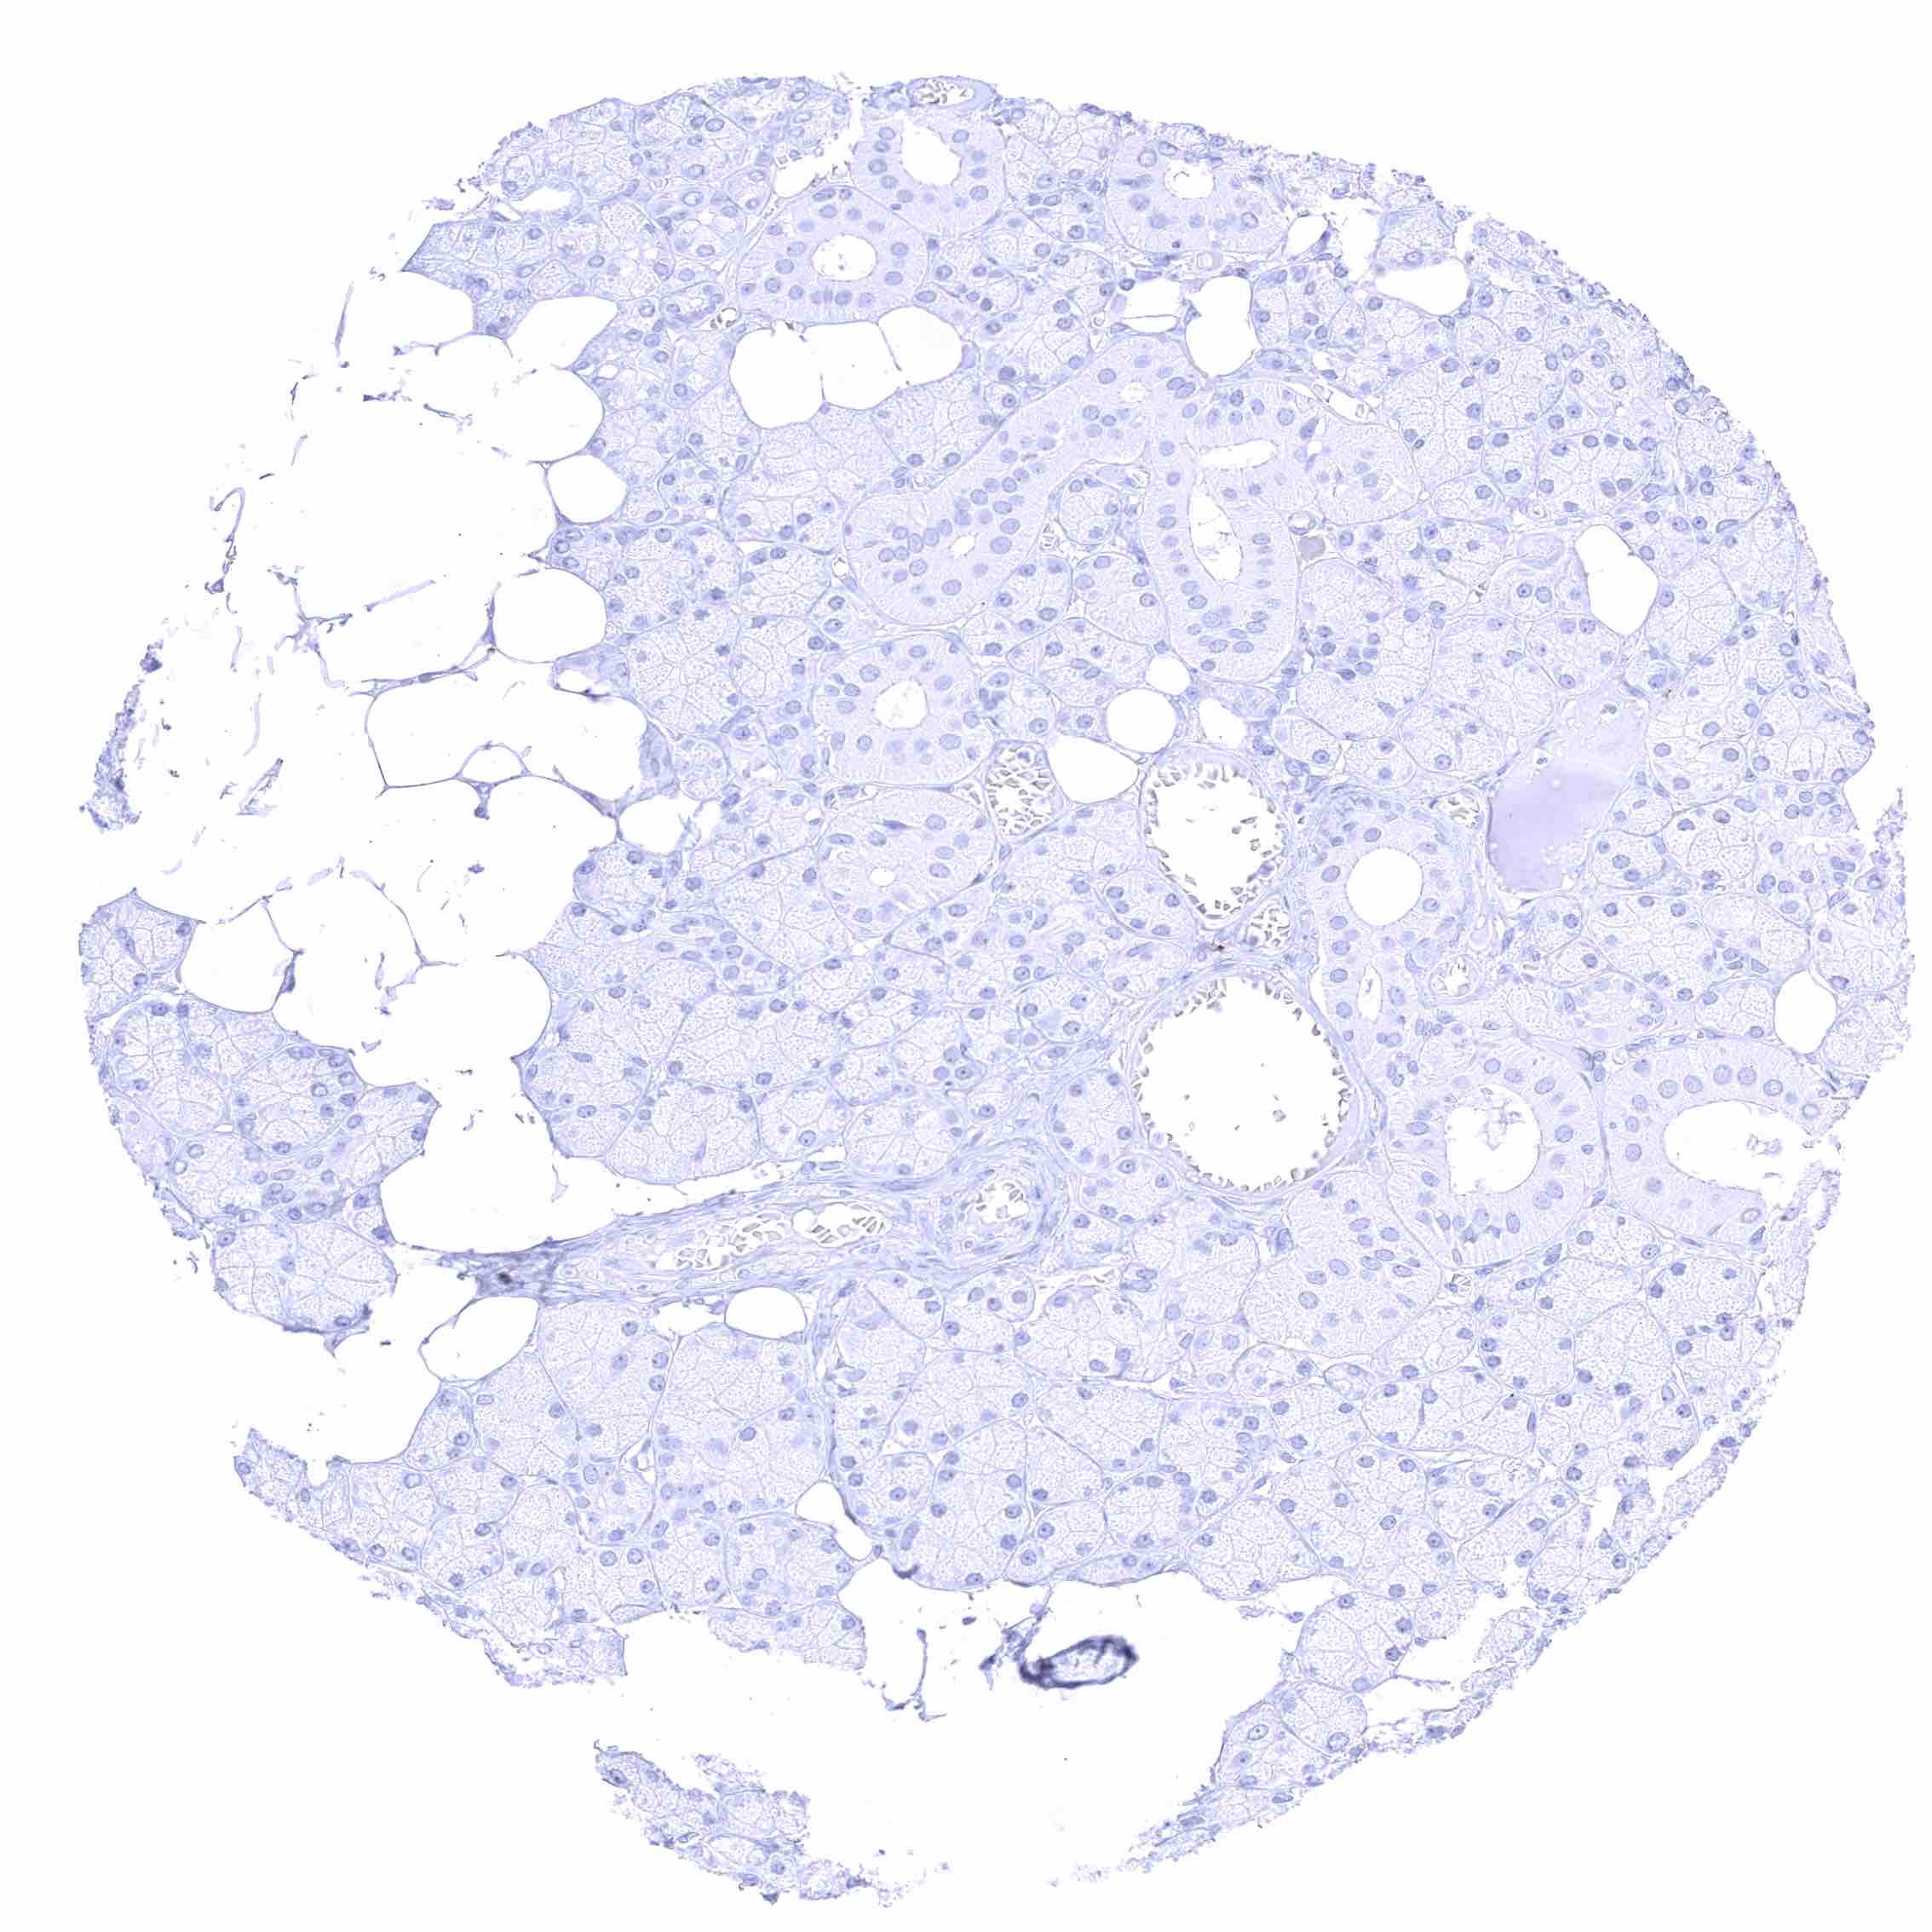

Kidney, cortex – Distinct CD70 membranous staining of the parietal layer of the Bowman capsule and of the luminal surface membrane of few tubuli which appear atrophic.

Kidney, cortex